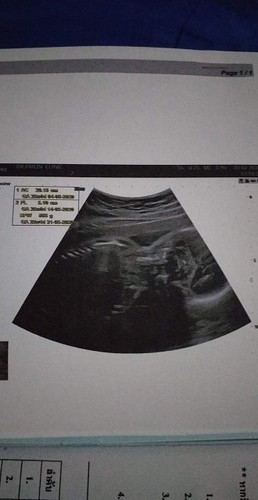

ดูยังไงว่าหญิงหรือชายแม่ๆช่วยดูหน่อยใครมีประสพการณ์บอกหน่อย

ภาพนี้ดูไม่ได้จ๊ะ ไม่ใช่มุมสำหรับดูเพศจ้า